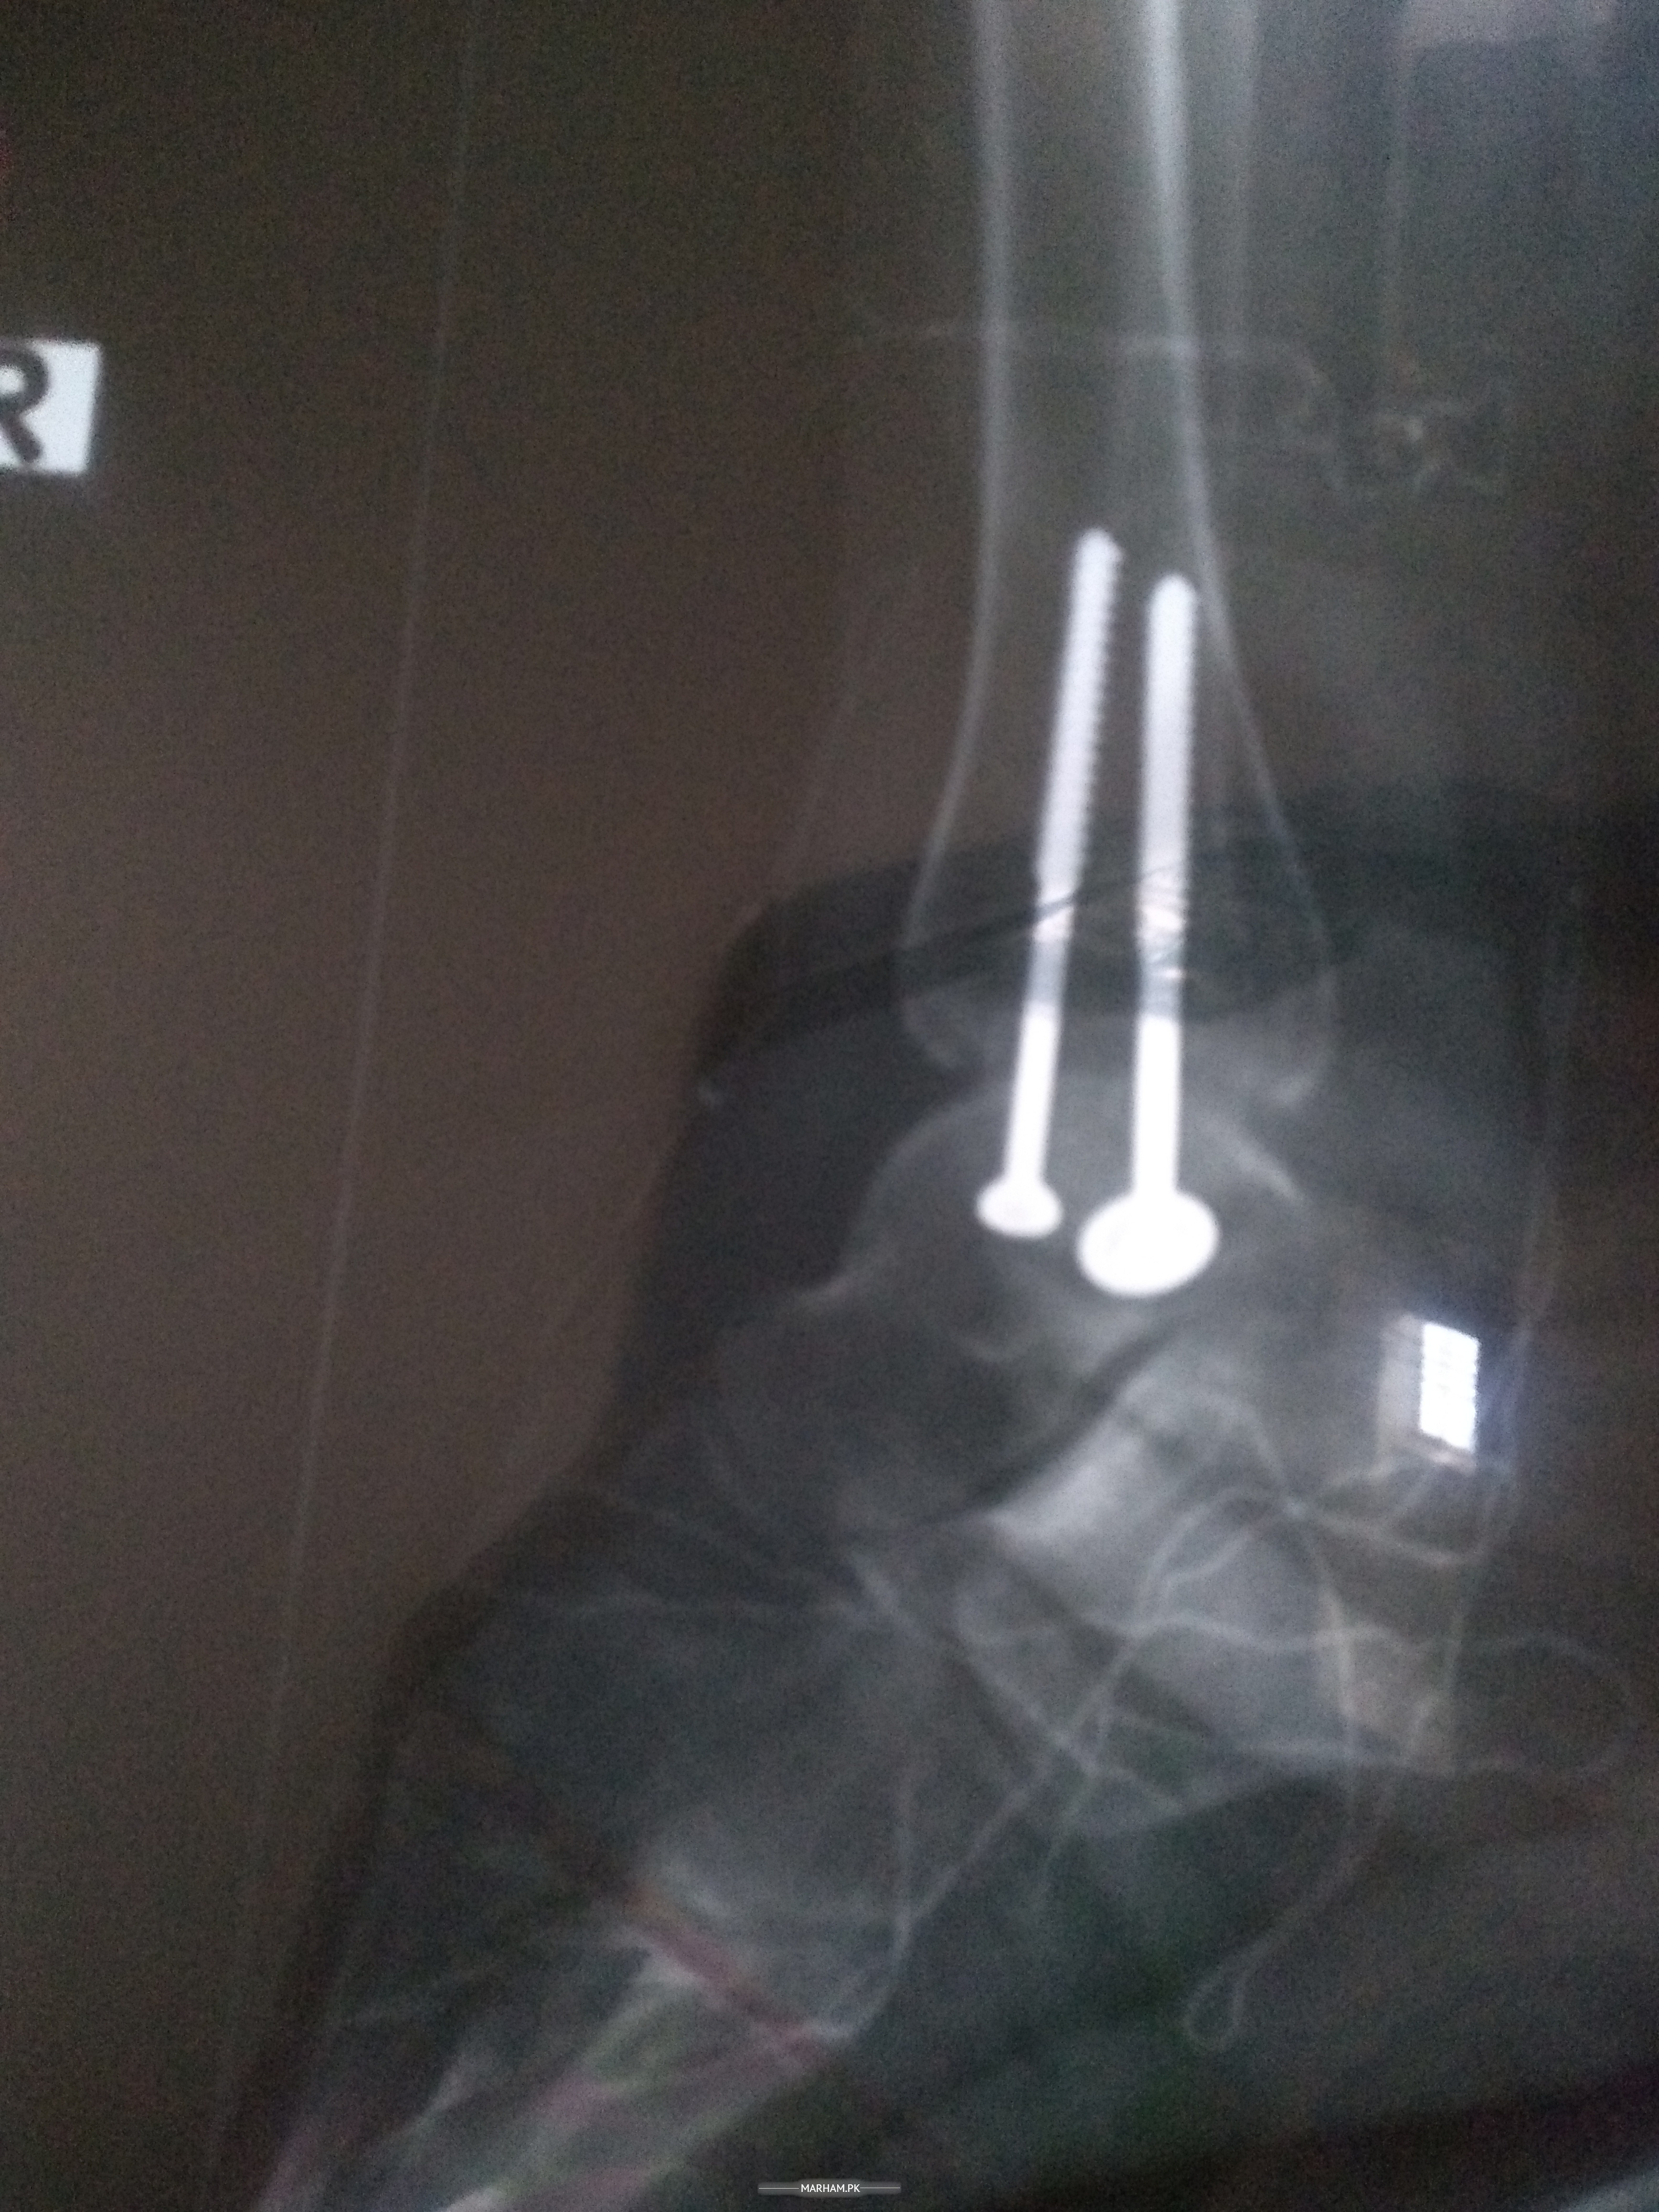

2 screw lge hue hen exercise krne se pain b hota Hy abi Mera 8 week start ho chka Hy Dr. vacation pr Hy is lye yahan pucha check my xray

4week xray

This is simple medial malleolar fixation of your ankle. Start partial weight bearing on this foot witb full range of movement exercises at ankle joint when in bed or chair. In next 2-4 weeks gradually start full weight bearing. You can start swimming and driving after 12 weeks of surgery (that is 6 weeks from now).